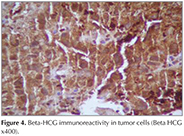

?A 43-year old male patient was admitted with dyspnea and chest pain. On physical examination the breath sounds were markedly diminished at right hemithorax and he had bilateral gynaecomastia. He was a smoker and his smoking history was 22 pack years. A chest radiograph showed opacity involving all zones of right hemithorax and nodular opacities at left hemithorax (Figure 1). A thorax computed tomography (CT) revealed a mass lesion occupying almost all right hemithorax and multiple masses in the left hemithorax. There was also pleural effusion and compression atelectasis at right hemithorax. Laboratory studies revealed a normal complete blood count and serum biochemistry. The erythrocyte sedimentation rate was elevated. Since he was a young patient, had bilateral multiple masses at thorax CT and also had gynaecomastia, a germ cell tumor was suspected and serum β-HCG level was analyzed. The serum β-HCG level was found as elevated: 4261 mIU/mL (normal less then 2.0). Positron emission tomography (PET)-CT revealed pathologic 18 FDG uptake at mass lesions in both hemithorax and mediastinal lymph nodes (Figure 2). Positron emission tomography and ultrasonography showed no gonadal involvement. A bronchoscopy was performed and an endobronchial lesion at the apical segment of right upper lobe was observed. A definitive diagnosis was not achieved by pathologic examination of biopsy specimen, bronchoscopy was repeated and samples were taken by cryobiopsy. Tumor consisted of solid sheets of uniform large tumor cells (Figure 3). Tumor cells were positive with P63 and β-HCG (Figure 4). Keratin 5/6, TTF-1, PLAP and AFP were negative in tumor cells. Mucine carmin staining was negative. We didn't observe syncytiotrophoblast and cytotrophoblast. Our case was β-HCG secreting nonsmall cell lung carcinoma. Since the patient was inoperable, a chemotherapy protocol was started.